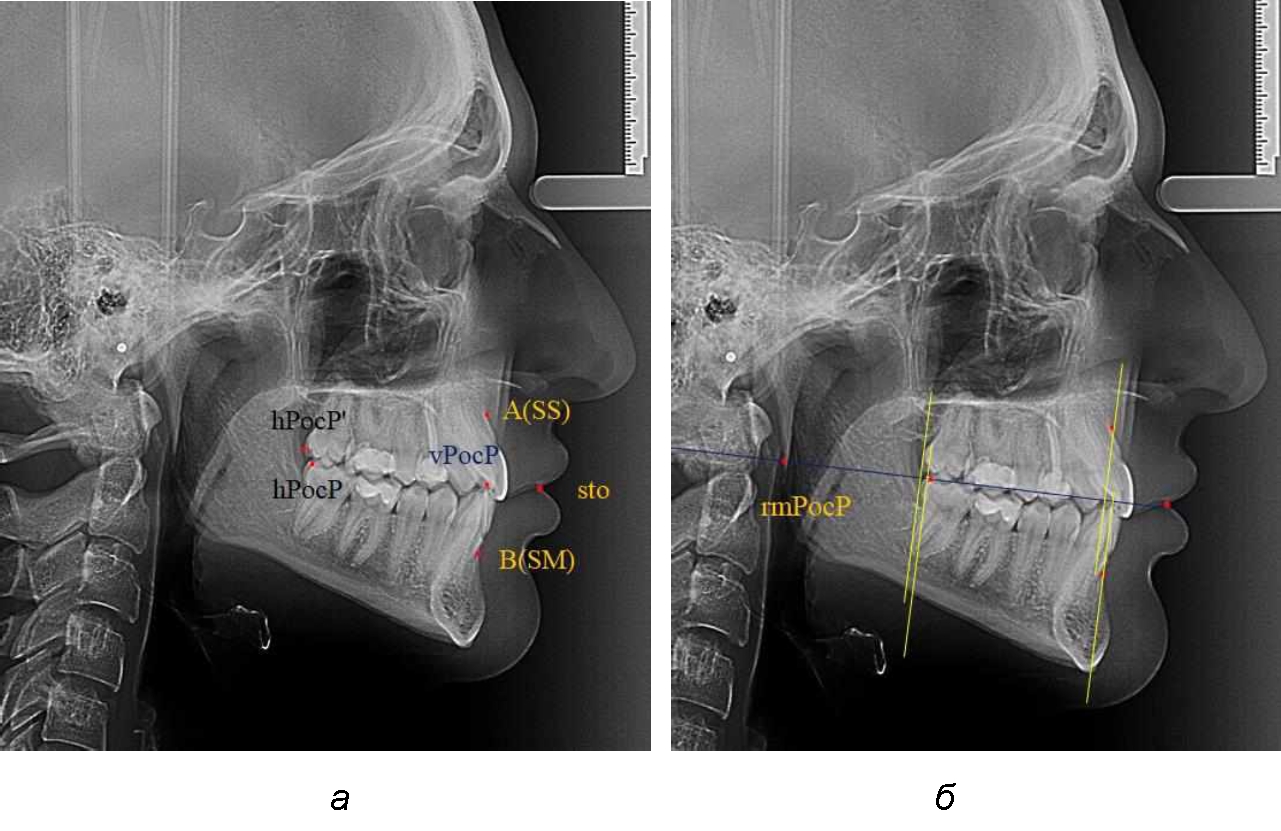

На рентгенограммах устанавливали точки Downs. На верхней челюсти субспинальная точка A(SS) располагалась в наиболее вогнутой точке альвеолярного отростка по переднему его краю. На нижней челюсти супраментальная точка B(SM) соответствовала месту наибольшей вогнутости переднего края альвеолярной части. Окклюзионную линию проводили через контактную точку резцов (vРOcP) и дистальную точку окклюзии второго нижнего моляра (hРOcP). Место пересечения окклюзионной линии с дистальным краем ветви нижней челюсти (ramus mandibule) обозначали как «rmРOcP». Перпендикулярно к окклюзионной плоскости проводили линии из точек «А(SS)» и «В(SМ)», что определяло их проекцию на окклюзионную линию. Аналогично отмечали положения дистальных окклюзионных точек верхней и нижней челюсти (рис. 1).

Рис. 1. Положение основных точек (а) и линейных ориентиров (б) для анализа положения и размеров челюстей

Альвеолярно-дентальный размер верхней челюсти и нижней челюсти оценивали по окклюзионной линии между вертикалями, ограничивающими исследуемые челюсти. Положение верхней челюсти оценивали по величине размера «rmOcP-А», а нижней челюсти по расстоянию «rmOcP-В». Линия смыкания губ обозначалась как точка «sto», вблизи которой проходила окклюзионная линия. Данный ориентир позволял провести окклюзионную плоскость при аномалиях положения резцов в вертикальном направлении, когда была сложность определения резцовой окклюзионной точки (vРOcP).

При сагиттальной патологии прикуса встречались варианты, при которых отмечалось равенство либо не равенство альвеолярно-ден-тальных размеров челюстей. Однако вне зависимости от этого, как правило, была отмечена разница в положении челюстей, измеряемая от конструируемой точки «rmРOcP» до точек апикальных базисов по Downs. С дистальной окклюзией было 20 снимков и с мезиальной окклюзией – 19 снимков.

Характерной особенностью мезиальной окклюзии было увеличение расстояния между проекционными апикальными точками, при котором существенно смещалась кпереди нижняя челюсть, а Wits-число имело отрицательные значения. Также дистальная точка нижнего моляра была расположена кпереди от верхней дистальной точки окклюзии второго моляра. Относительно равными считались показатели альвеолярно-дентальных размеров, при которых разница не превышала 1,5 мм. Тем не менее расстояние «rmРOcP-B(SM)» превышало расстояние «rmРOcP-A(SS)» в среднем по группе на (6,87 ± 1,62) мм, что свидетельствовало об аномалии положения челюстей, при котором визуально нижняя челюсть располагалась впереди верхней челюсти (рис. 3).

Рис. 3. Положение апикальных точек и челюстей при мезиальной окклюзии с равными (а) и разными (б) альвеолярно-дентальными размерами зубо-челюстных дуг

В тех случаях, когда при мезиальной окклюзии альвеолярно-дентальные размеры были различными, размер нижней челюсти превышал аналогичный параметр верхней челюсти в среднем на (3,74 ± 1,28) мм.

На рентенограммах с признаками дистальной окклюзии Wits-число имело положительные значения. Дистальная точка нижнего моляра была расположена позади верхней дистальной точки окклюзии второго моляра. Относительно равными, так же как и при анализе снимков с мезиальной окклюзией, считались показатели альвеолярно-дентальных размеров, при которых разница не превышала 1,5 мм. Тем не менее расстояние «rmРOcP-A(SS)» превышало расстояние «rmРOcP-B(SM)» в среднем по группе на (5,29 ± 1,47) мм (рис. 4).

Рис. 4. Положение апикальных точек и челюстей при дистальной окклюзии с равными (а) и разными (б) альвеолярно-дентальными размерами зубочелюстных дуг

В тех случаях, когда при дистальной окклюзии альвеолярно-дентальные размеры были различными, размер нижней челюсти превышал аналогичный параметр верхней челюсти, в среднем на (3,62 ± 1,12) мм.